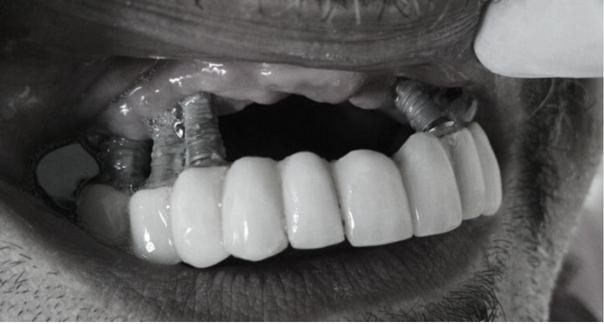

Như trong ảnh bên dưới, chỉ có phần đầu của chân răng implant bị mắc kẹt trong nướu,

có thể thấy nó dính chặt vào nhau như thể sắp rụng ra.

Khu vực cấy ghép răng phía trước của bệnh nhân thực tế có tình trạng tương tự như ảnh bên dưới.

(Trước khi điều trị tôi không biết ảnh miệng của bệnh nhân nên đã xóa và thay bằng ảnh để tham khảo.. ^^;;)

Nguồn : www.peri-implantitis.info